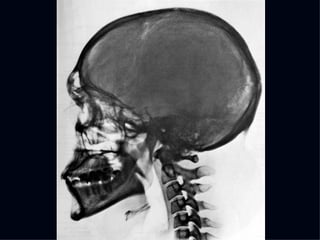

The document discusses the contributions of various figures in the field of medical imaging, including Wilhelm Röntgen and his discovery of X-rays, and the development of CT imaging and MRI technology. It highlights the historical significance of early imaging techniques and the initial skepticism from medical professionals regarding their usefulness. Key milestones in imaging are noted, along with the eventual acceptance of such technologies in clinical practice.